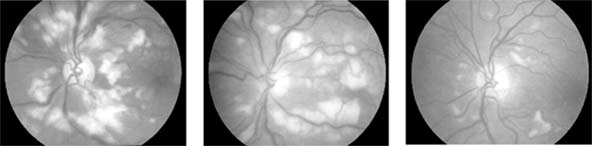

Figure 15-4

Figure 15-4: Cotton-wool spots. Numerous cotton-wool spots are seen in the posterior poles in three patients. Left: A young woman with acute systemic lupus erythematosus and neurologic disease. Center: A young man with pancreatitis. Right: A patient with AIDS. Cotton-wool spots resolve over 6 weeks regardless of their cause.